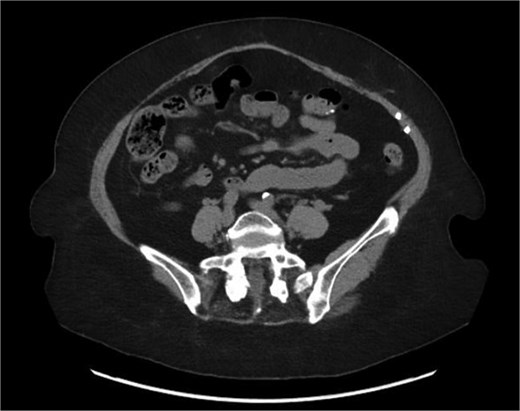

A 76-year-old female with a medical history of type 2 diabetes mellitus (controlled with oral medications), hypertension (on two medications), hyperlipidemia (on atorvastatin), and recently diagnosed Alzheimer’s disease (started on memantine) presented to the emergency department with severe left-sided abdominal pain of 2 days’ duration. The pain began gradually but worsened significantly in the last few hours. It was associated with a bulging mass in the abdomen that was tender and painful to touch. The patient reported that the swelling had been present for 2 years, intermittently reducible with minimal exertion. However, since the previous day, it had become irreducible and increasingly painful, particularly after a failed attempt to reduce it manually at home. She also admitted to chronic constipation for years, usually treated with oral laxatives, though she had not been compliant with them recently. Her surgical history included a laparoscopic cholecystectomy combined with paraumbilical hernia repair using mesh 3 years ago. Upon examination by the on-call surgical team, the patient was afebrile with stable vital signs. Her abdomen was distended, and a 7 × 7 cm irreducible, tender mass was noted over the left side. An urgent computed tomography (CT) scan of the abdomen and pelvis with intravenous and oral contrast revealed a left lateral ventral abdominal hernia traversing the left lateral oblique muscles. The hernia sac contained omental fat and an inflamed diverticulum of the transverse colon, with surrounding inflammatory changes. The defect measured 1.4 × 1 cm, and the hernia sac measured 6.7 × 4.2 × 4 cm. No free fluid, fluid collections, or pneumoperitoneum were identified (Figs 1–3).

Coronal section of CT abdomen and pelvis showing the ventral hernia.